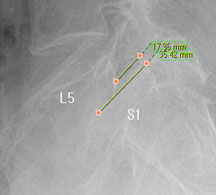

모커리한방병원 성○○ (53, 여) 척추전방전위증 2단계 실제치료사례 이미지

성○○ (53, 여) 척추전방전위증 2단계 입원치료기간 : 20일

입원시 퇴원시

허리 통증지수(NRS) 8 4

통증없이 걷는거리(m) 8분(400m) 20분(1km)